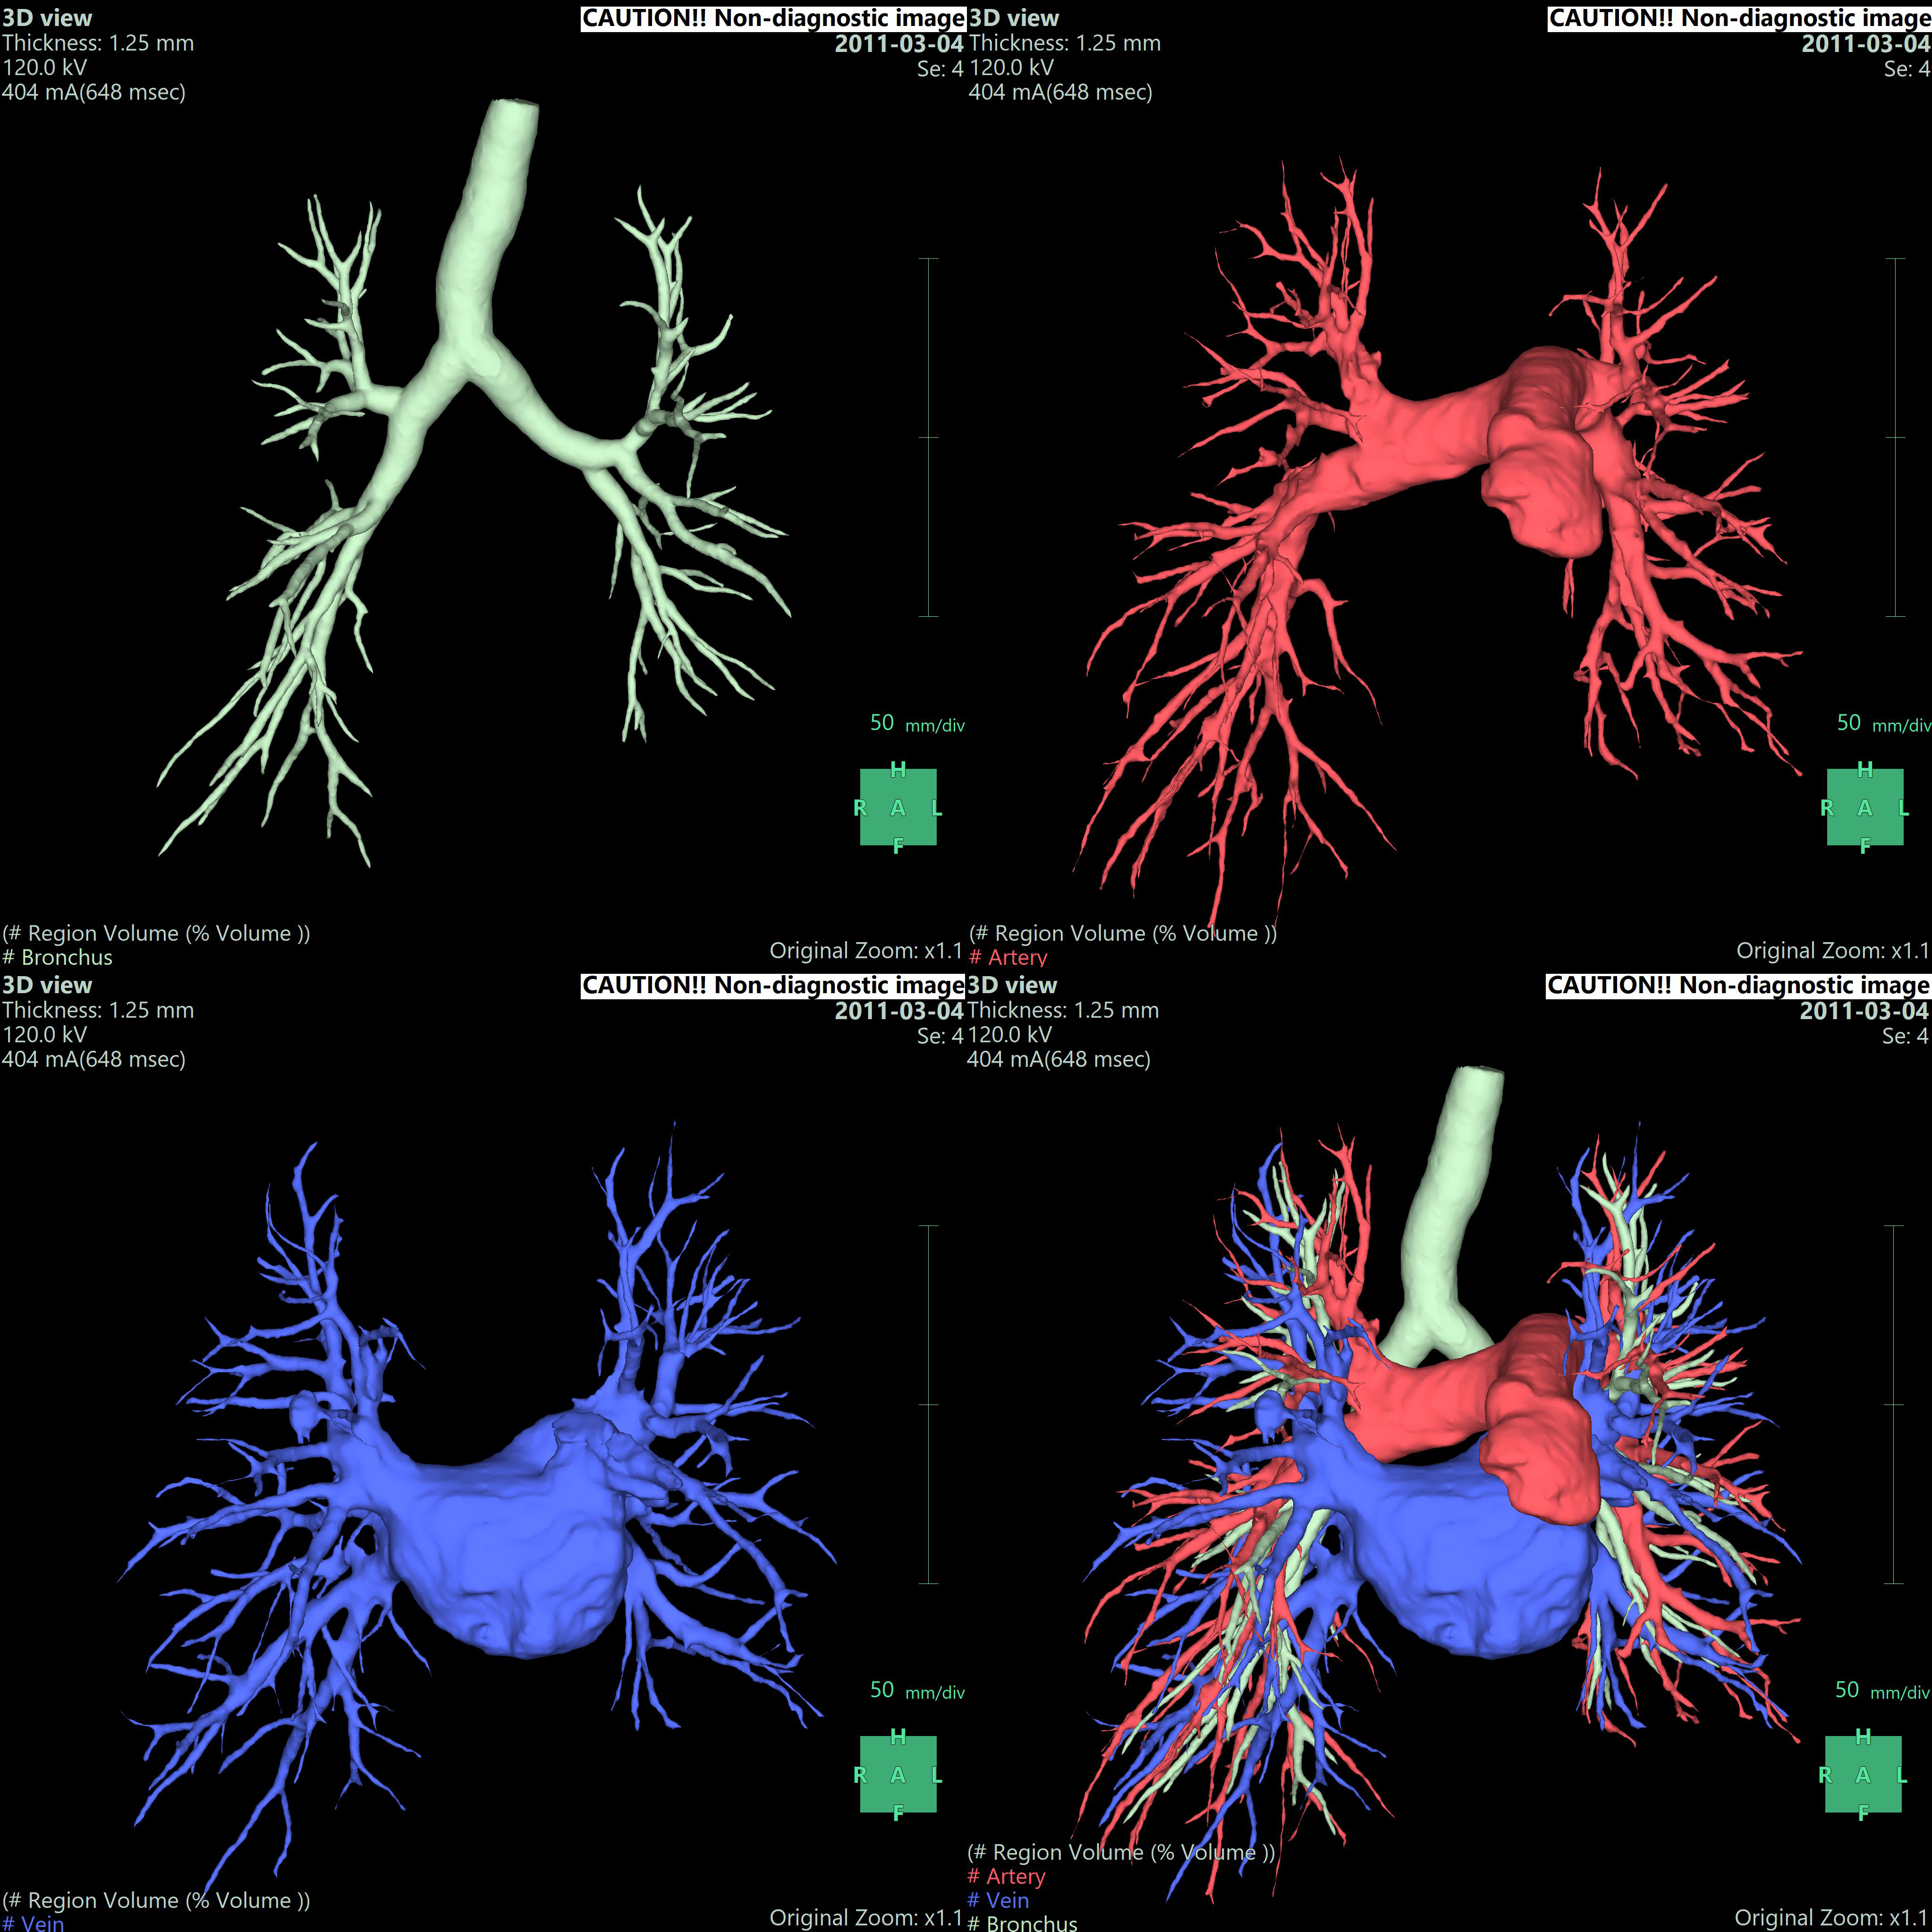

• - 조영 증강된 CT image를 사용하여 Lung, Airway, Vessel, tumor 등을 추출하고 3D로 재구성하고 결과를 관찰할 수 있습니다.

• - 임의의 Vascular point에서 territory를 분리하고 절제면, 절제면에서의 Vessel 및 territory의 volume 등을 측정할 수 있습니다.